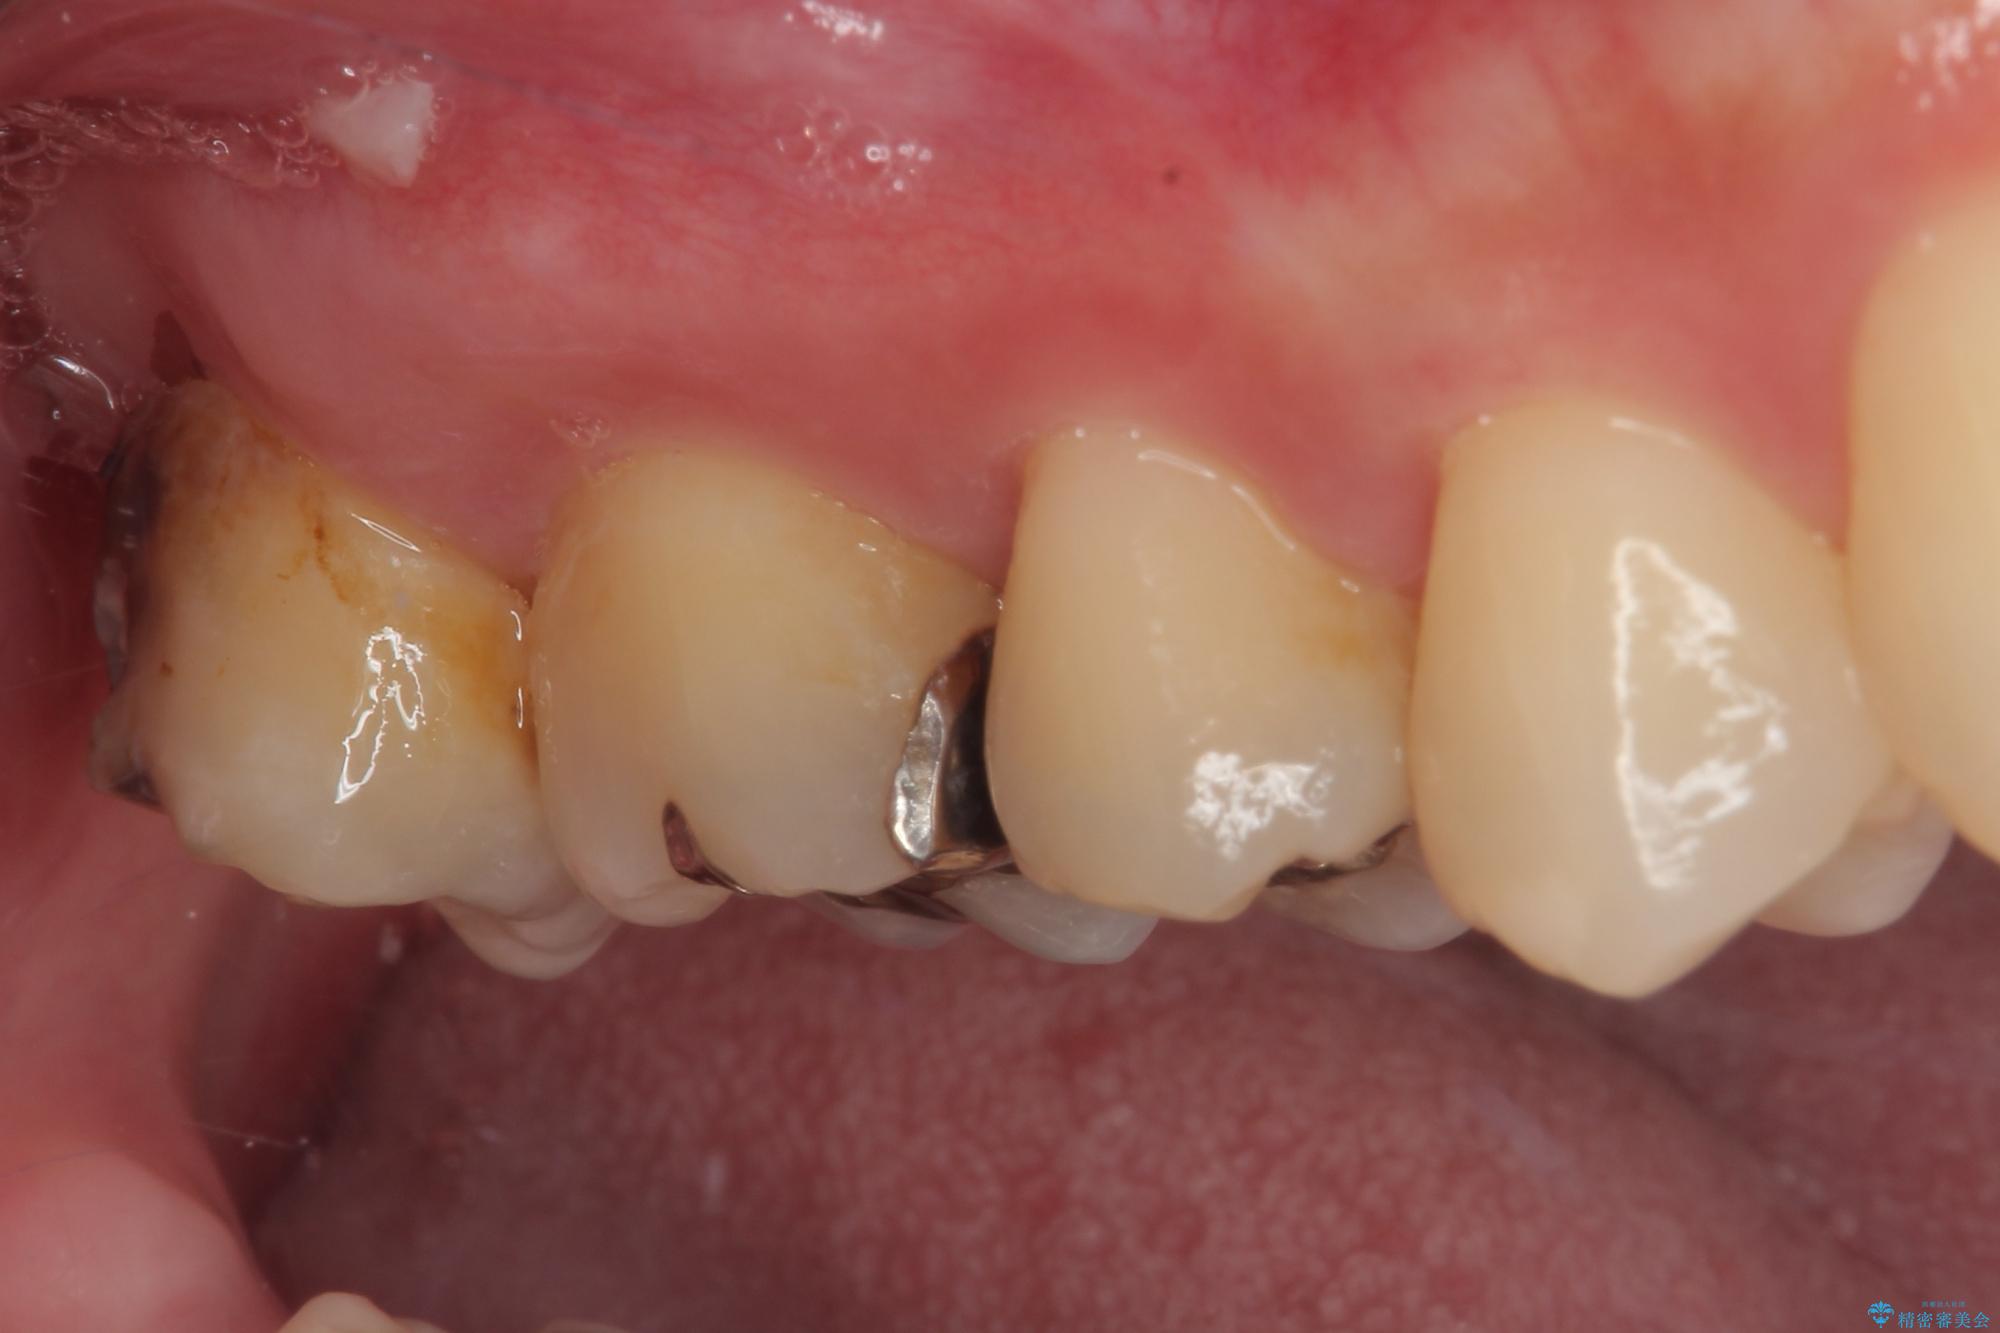

- 元々むし歯があったものの、処置が困難とのことでしたが、矯正治療を終えたので処置をしたいとのことで来院された患者様です。

左右ともに最後臼歯が頬側に顕著に突出しており、むし歯になってしまったことが想像されました。

矯正治療により処置が可能な位置に歯が移動したため、オールセラミッククラウンにて補綴治療を行うこととしました。

歯列が移動したとはいえ、左右ともに後方傾斜しており、むし歯の除去、形成(形を整える)、型取りの全てが非常に困難な処置となりました。